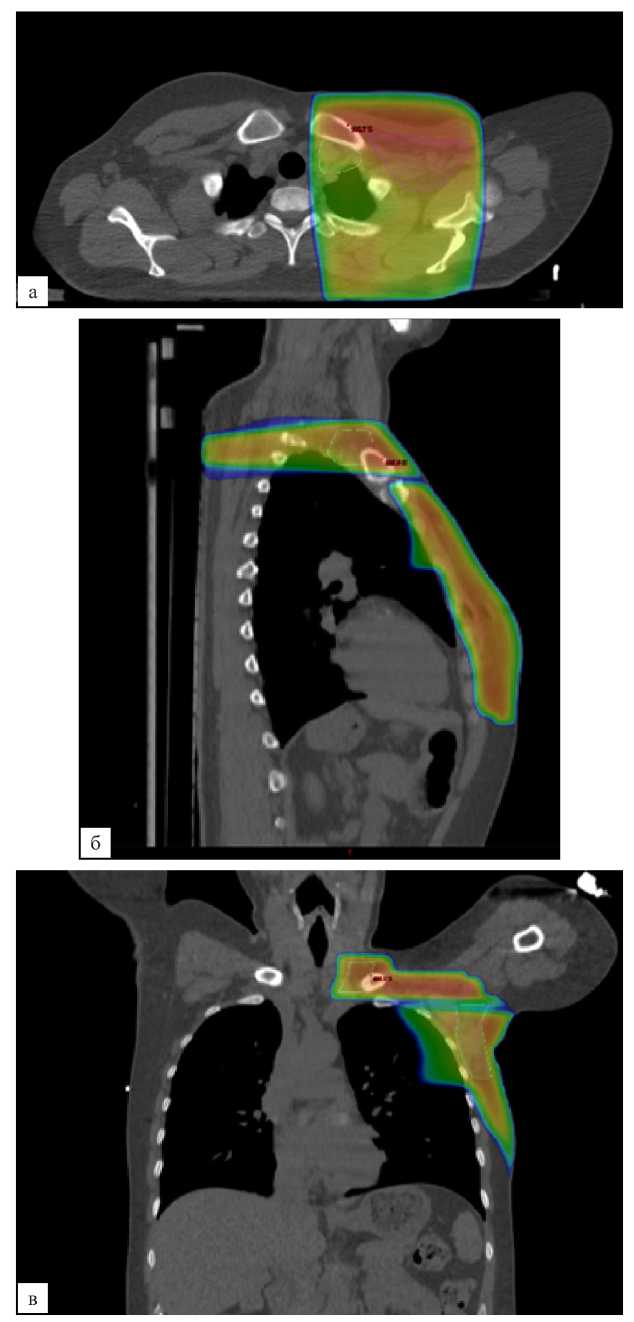

В контрольной группе послеоперационная лучевая терапия проводилась в стандартном объеме — облучение оставшихся тканей молочной железы (после органосохраняющего лечения) или мягких тканей передней грудной стенки (после мастэктомии) с подмышечными ЛУ I, II, III уровней и надключичными ЛУ (рис. 2, а, б, в). При планировании объемов облучения в исследуемой группе из объема облучения исключались подмышечные ЛУ III уровня и надключичные ЛУ (рис. 3, а, б, в). Оконтуривание всех указанных структур выполнялось согласно рекомендациям ESTRO от 2015 года [15].

Рис. 3 (а, б, в). Дозиметрический план лучевой терапии молочной железы и подмышечных лимфатических узлов I, II уровней. а — аксиальная проекция; б — сагиттальная проекция; в — фронтальная проекция

Fig. 3 (а, б, в). Dosimetric plan for the breast RT, axillary lymph nodes of levels I, II. a — axial plane; б — sagittal plane; в — frontal plane